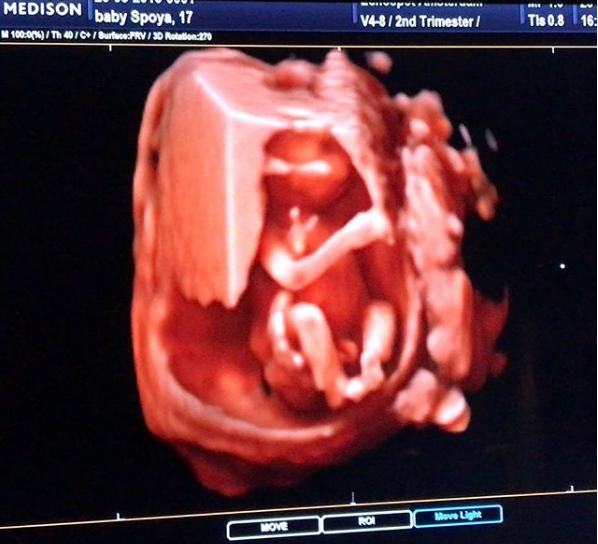

La modelo Laura Spoya decidió compartir con todos sus seguidores la ecografía de sus 17 semanas de embarazo. Y es que la ex Miss Perú suele subir a su cuenta de Instagram el desarrollo de su periodo de gestación.

La influencer también reveló el sexo de su bebé a través de un video en youtube. Pero en esta ocasión, quiso mostrar la ecografía que se realizó a las 17 semanas de embarazo. La fotografía conmovió a todos sus seguidores en la red social.

“Emilia “La Britany” los saluda. Algo me dice que esta baby va a ser una Laurita corregida y aumentada”, escribió Spoya en la descripción de la imagen en Instagram.

Echa un vistazo a la foto: